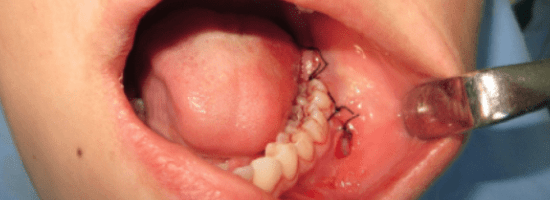

Frenectomy

Frenectomy is a minor surgical procedure that involves removing or repositioning the prominent tissue flap (frenum) beneath the upper lip. When this tissue is too thick or extended, it can interfere with denture fitting or cause a gap between the upper front teeth.